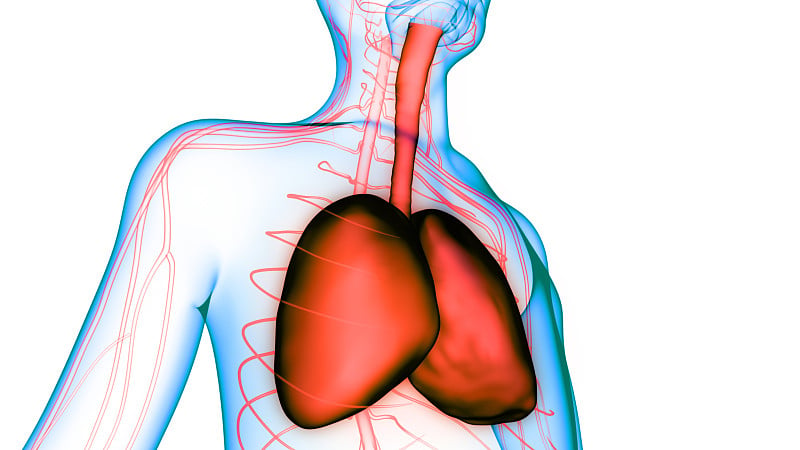

人体呼吸系统肺解剖学详情

JPG